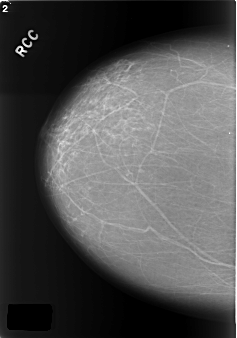

C_0176_1.RIGHT_CC

RIGHT_CC LINES 5736 PIXELS_PER_LINE 4024 BITS_PER_PIXEL 12 RESOLUTION 50 NON_OVERLAY